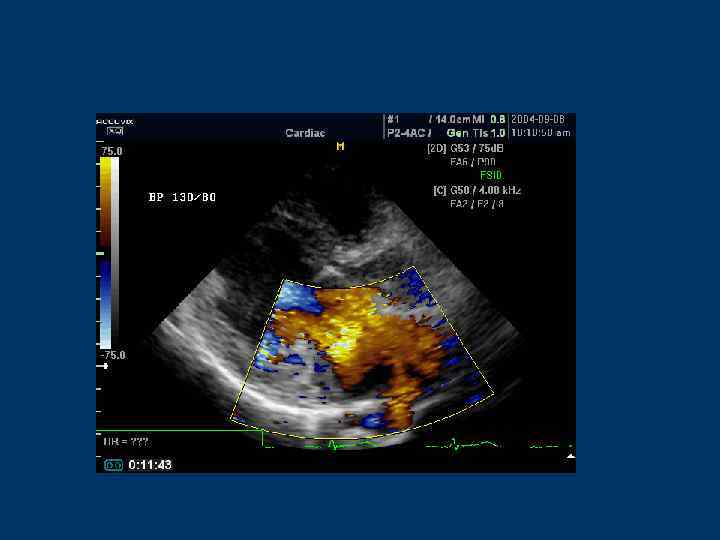

Цветное допплеровское сканирование (Color Doppler)

Color Doppler